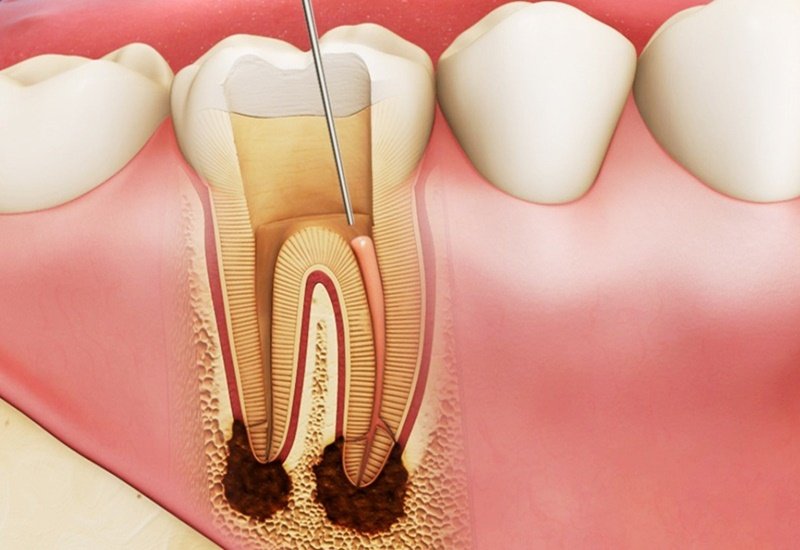

Trước hết, bạn cần hiểu về tủy răng. Tủy răng nằm ở hốc giữa ngà răng và bao gồm nhiều tổ chức khác nhau như mạch máu, thần kinh,… Tình trạng viêm ở tủy và các mô quanh chân răng được gọi là viêm tủy răng. Đây là phản ứng của tủy để chống lại những tác nhân gây bệnh.

- Trường hợp trên răng đã xuất hiện những lỗ sâu lớn, những vết gãy và vi khuẩn xâm nhập và gây viêm tủy, người bệnh sẽ cảm thấy đau buốt, thậm chí có sử dụng thuốc giảm đau mà không thấy đỡ. Khi nhai hoặc tiếp xúc với đồ ăn nóng hay lạnh thì cơn đau càng nghiêm trọng. Với những trường hợp này, các bác sĩ sẽ thực hiện điều trị tủy cho người bệnh. Khi được loại bỏ phần tủy có chứa nhiều vi khuẩn, những cơn đau sẽ dần thuyên giảm.

Nếu không kịp thời điều trị, bệnh sẽ tiến triển thành những ổ viêm ở chân răng và khiến cho việc điều tị tủy răng sẽ khó khăn hơn rất nhiều. Đồng thời, bệnh nhân có nguy cơ phải đối mặt với một số biến chứng nguy hiểm khác như chết tủy, thối tủy, viêm hạch, xương hàm và thậm chí là mất răng,...